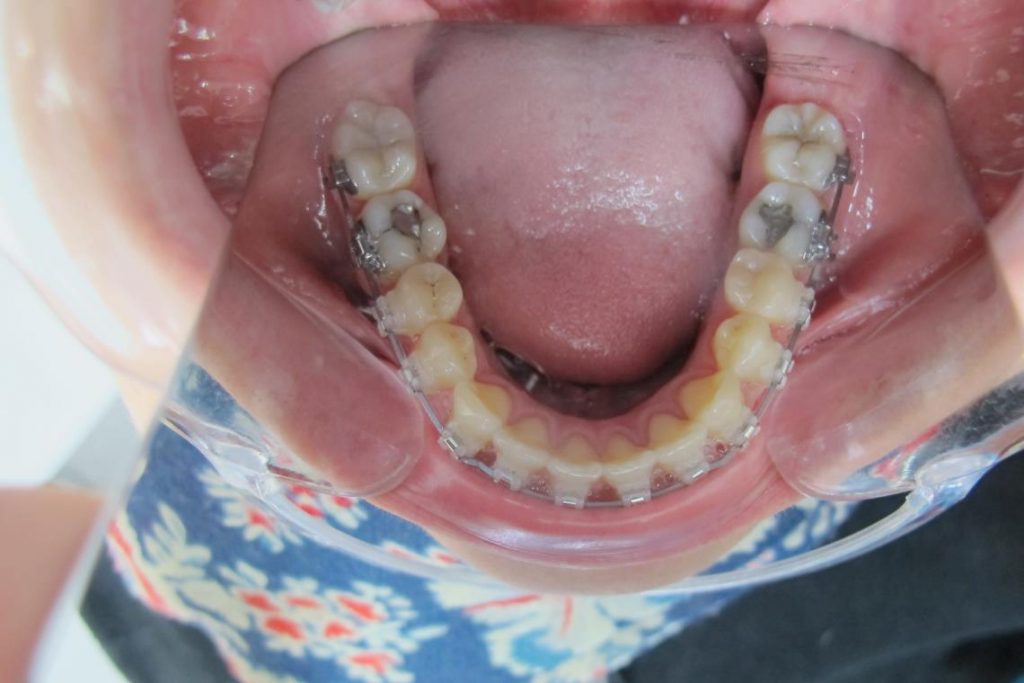

Après traitement orthodontique et réalisation d’une attelle fibrée (courtoisie Dr Patrick Fournier)